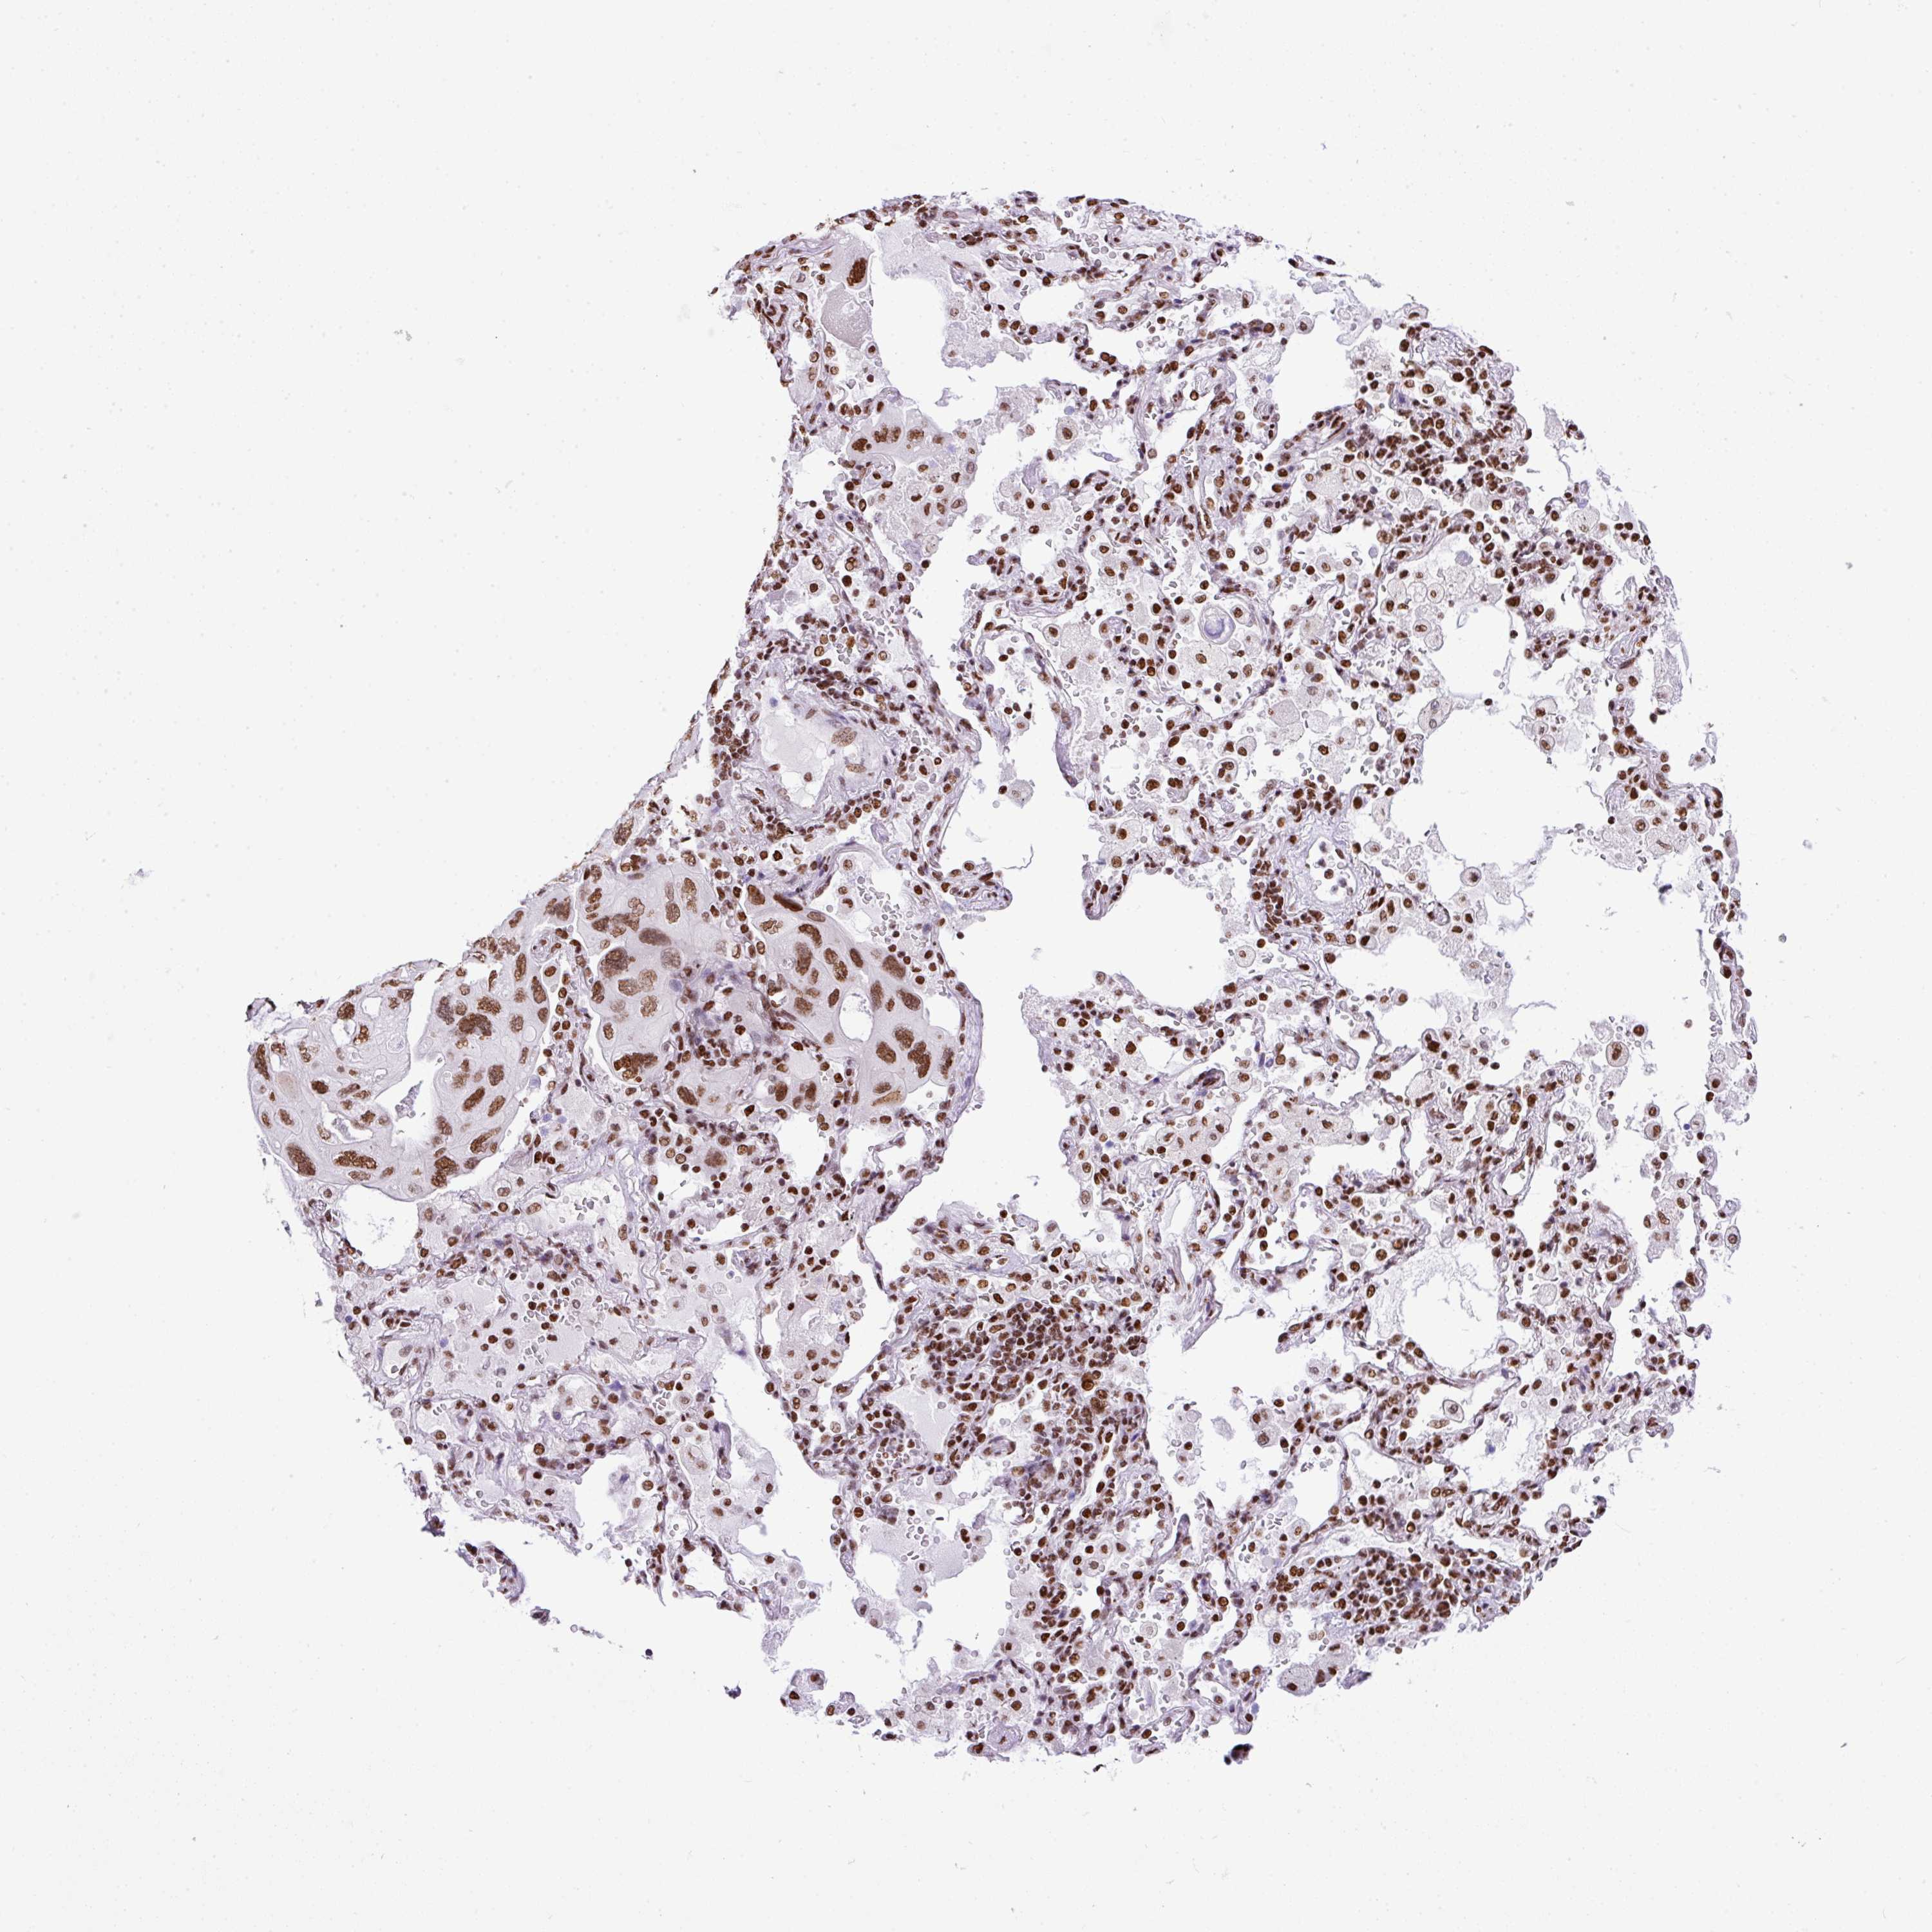

CANCER LUNG CANCER Show tissue menu

Lung cancer

Human cancer

Lung adenocarcinoma